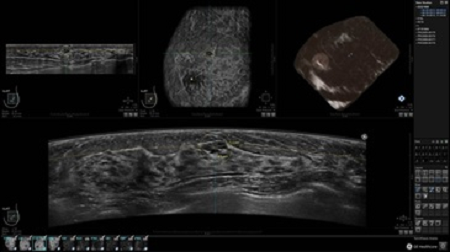

GE INVENIA ABUS – это современный УЗИ аппарат, который создан для точной и эффективной диагностики сканирования с высокой плотностью молочных желез. Выявляемость патологий раковых и предраковых стадий заболевания составляет 55%, что в конечном счете позволяет ставить врачу точные и своевременные диагнозы. Традиционные методы использования маммографии не показывают такой выявляемости, ограничиваясь лишь 3-38%.

УЗИ-аппарат GE INVENIA ABUS позволяет проводить максимально операторонезависимые процедуры, что значительно снижает риск неправильной постановки диагноза и сопутствующие издержки на обработку информации. Система готовит отчет в течение 3-х минут после сканирования, это безусловное преимущество по сравнению с обычным УЗИ сканером.

• датчик с изогнутой апертурой для качественного исследования

• сканирование одной грудной железы в трех проекциях не более 60 сек.;

• обработка результатов за три минуты.

• Получение объемных 3D изображений с возможностью покадрового просмотра

• Получение изображений в поперечной плоскости (в реальном времени) и в коронарной плоскости (статическая, для указания нахождения соска)

• Отображение объемных 3D ультразвуковых изображений, которые состоят из традиционных поперечных и воссозданных коронарных и сагиттальных проекций

• Стандартизованная ориентация изображения: «толстый срез» в коронарной плоскости; поперечная; сагиттальная плоскость; радиальный и антирадиальный поворот изображения; просмотр исключительно области интереса